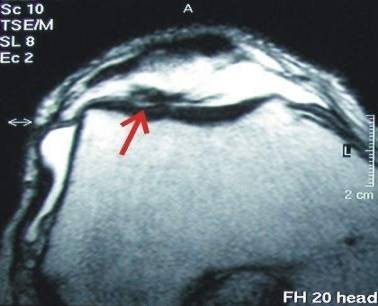

Full cartilage defect on patella plain

The patient feels pain at low load and even while resting.

Eighteen months after the cartilage repair the defect is completely filled and the patient is pain-free and fully capable of engaging in sports.